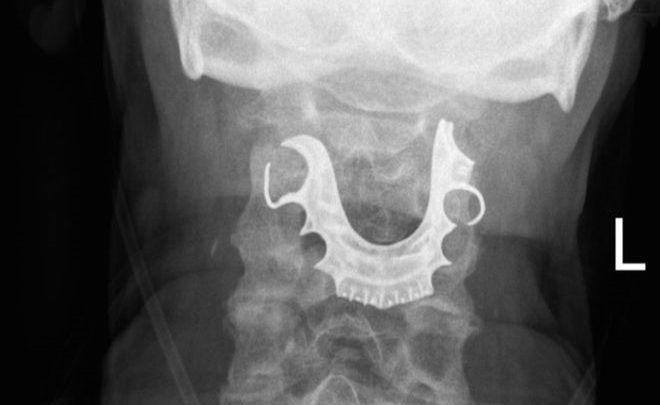

ولكن لما عاد الرجل إلى المستشفى بعد يومين، فحص فريق الأطباء حلقه وحنجرته ليجدوا شيئا شبه دائري يقبع على أحباله الصوتية.

ثم لم يلبث أن أخبر الأطباء عن فقدانه طقم أسنانه أثناء إقامته في المستشفى وخضوعه للجراحة.